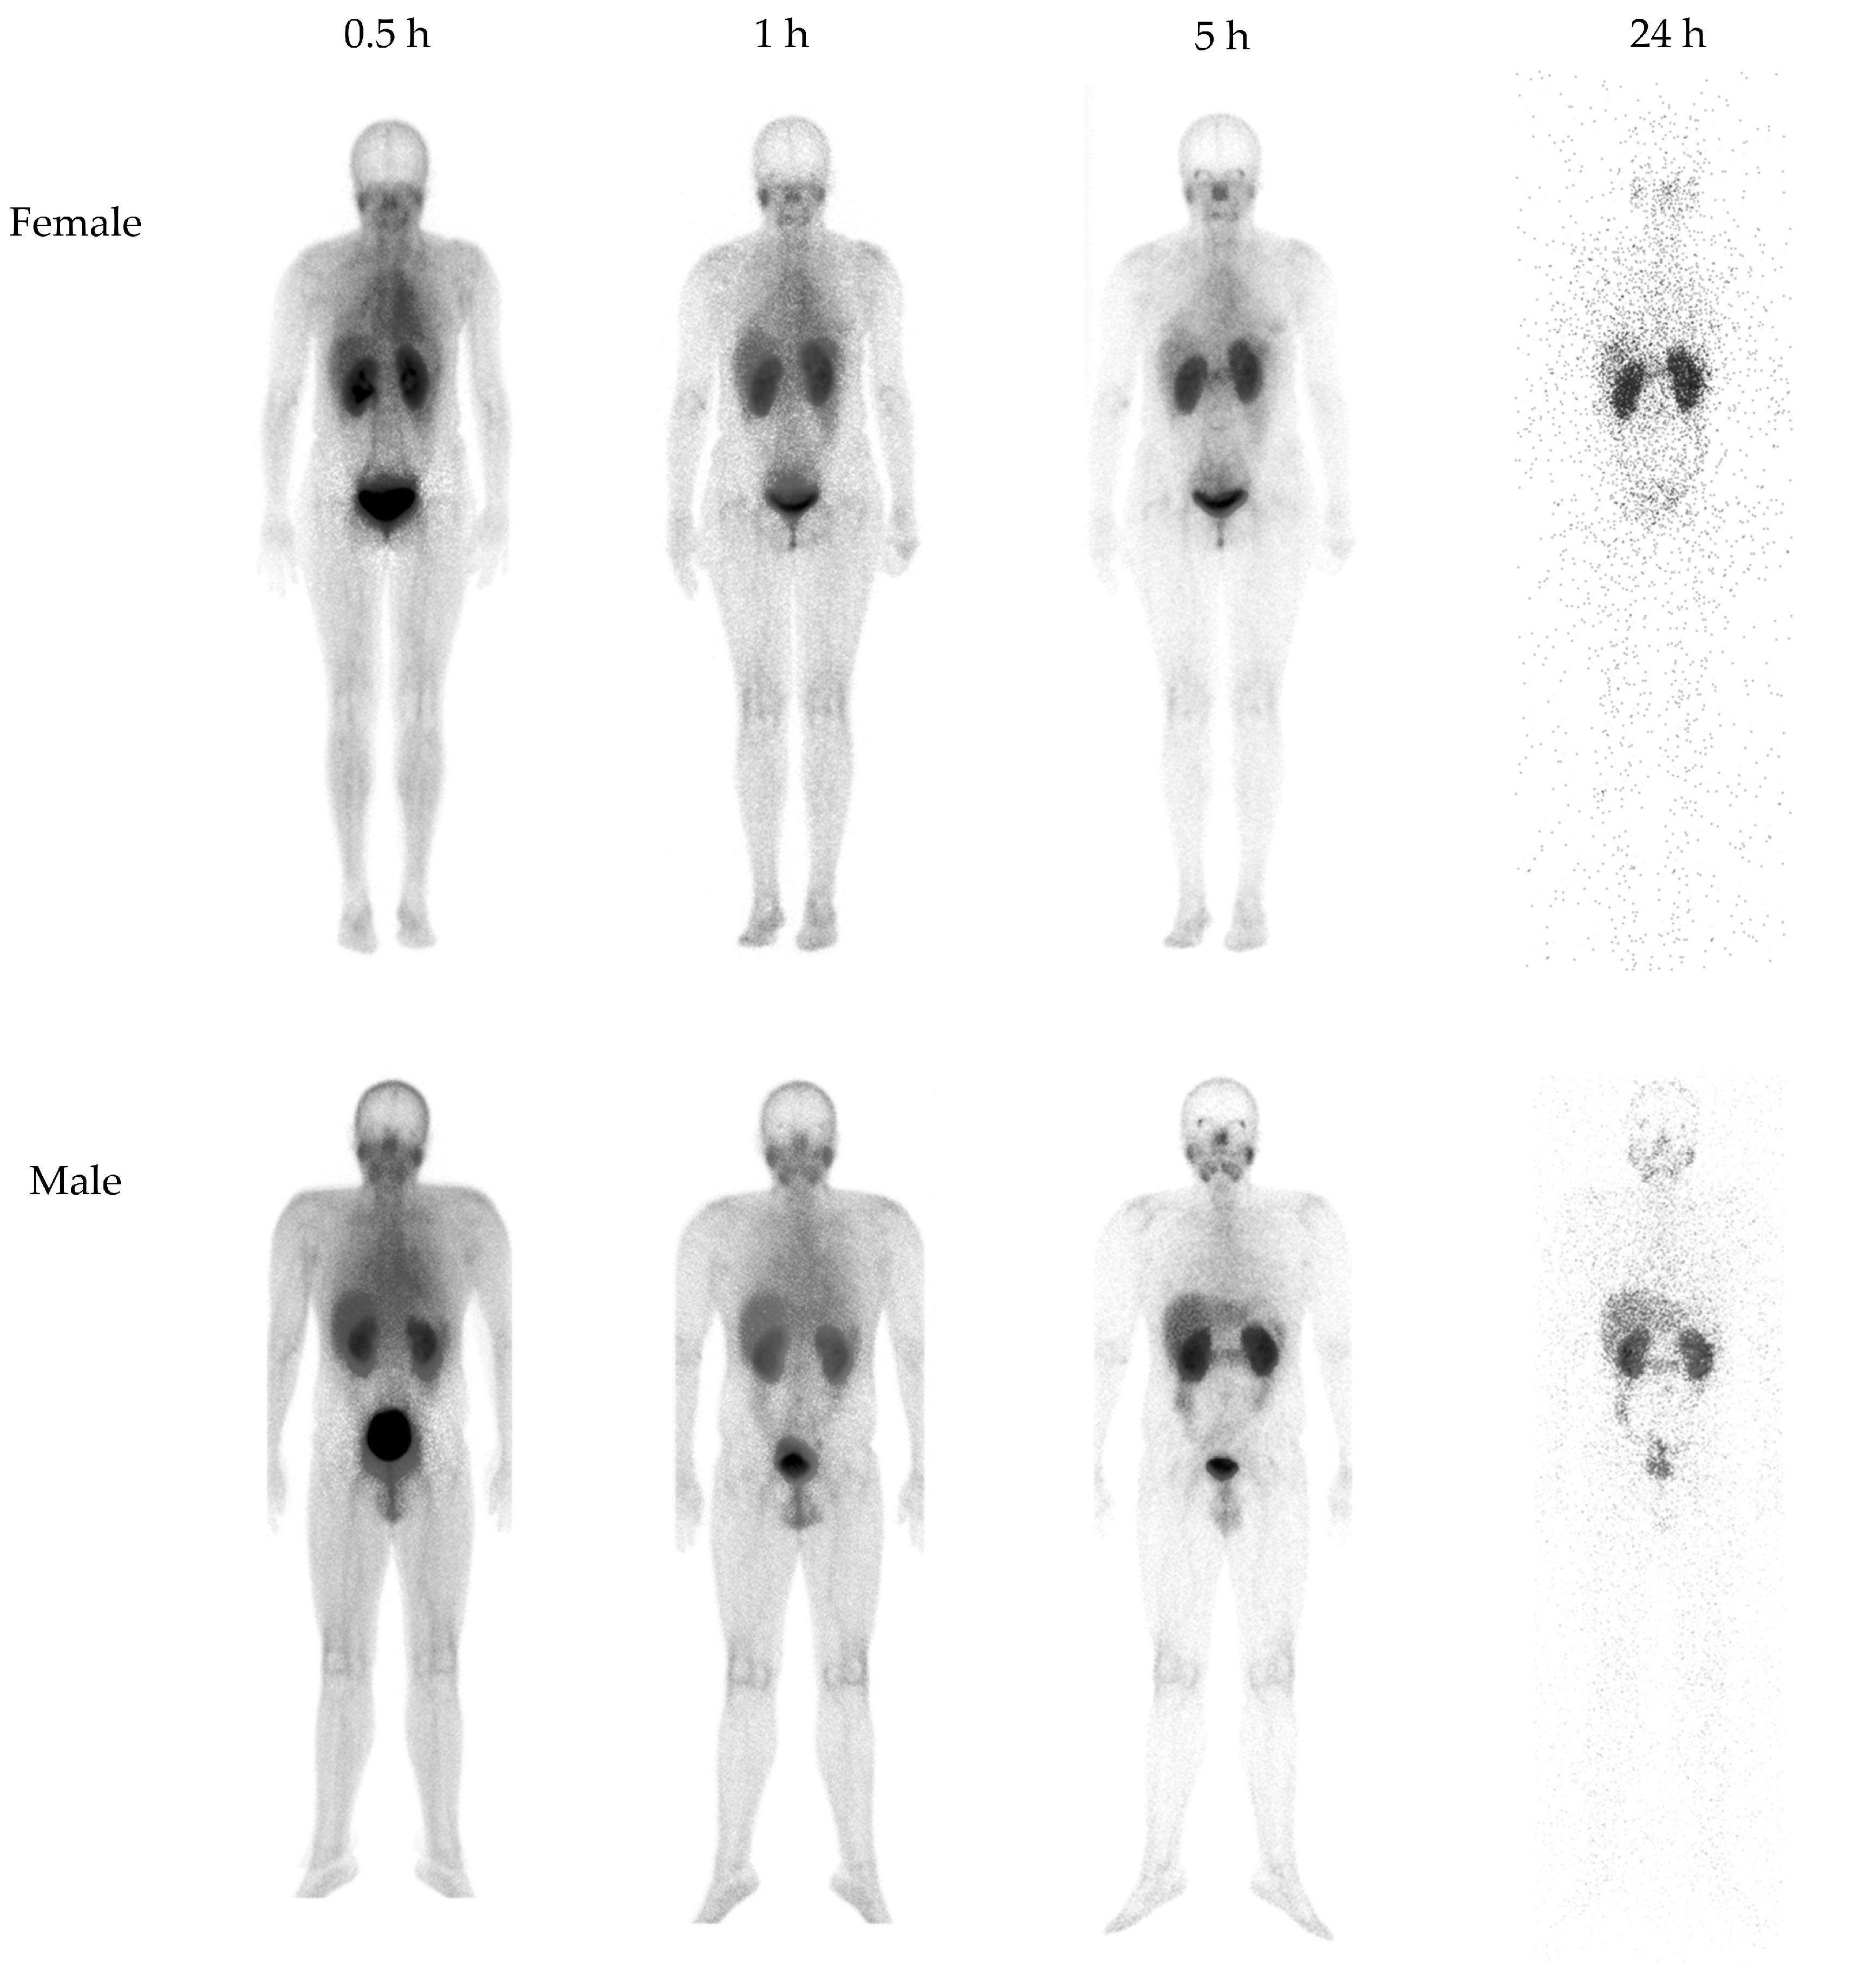

3.2.1. Biokinetics and Dosimetry

3.2.2. Imaging in Patients